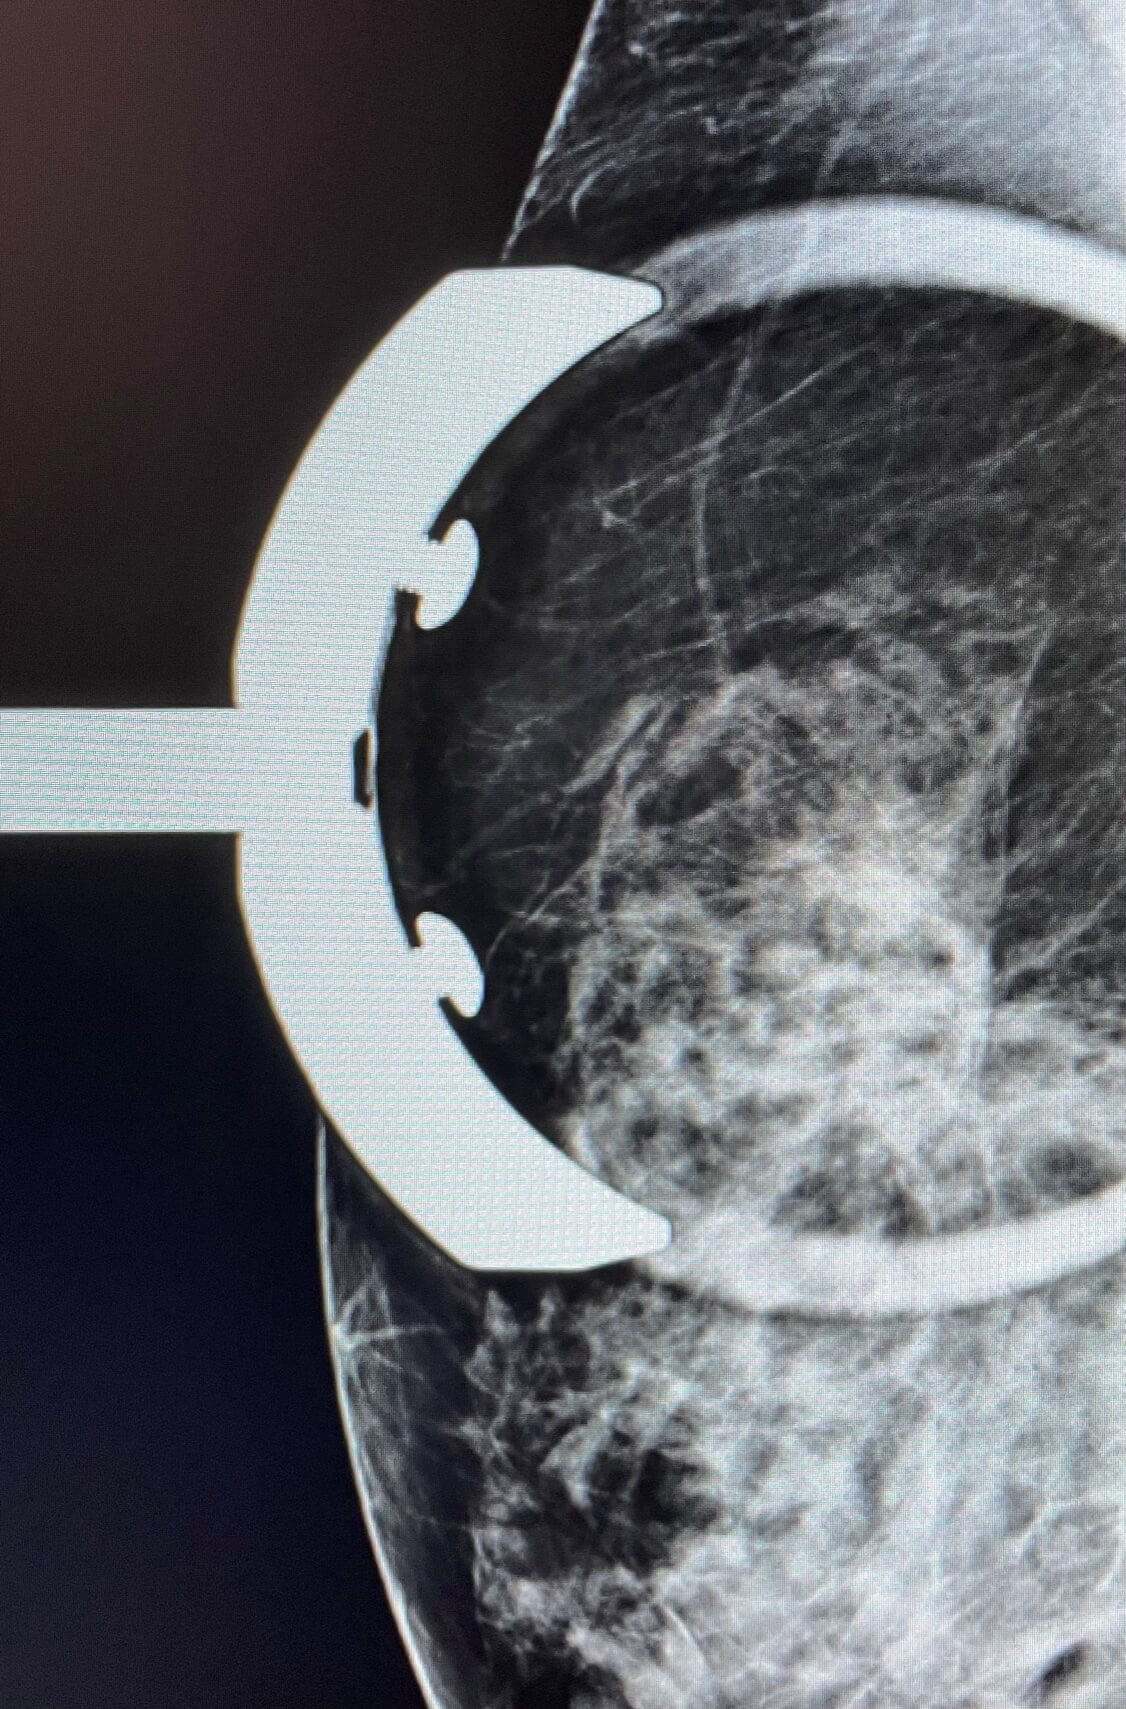

MammoScreen® shows an architectural distortion of the right breast.

Ultrasound shows a hypoechoic mass with irregular contours, with stiffness from the shearwave elastography.

The biopsy performed confirms an infiltrating lobular carcinoma ER/PR+, Her2+